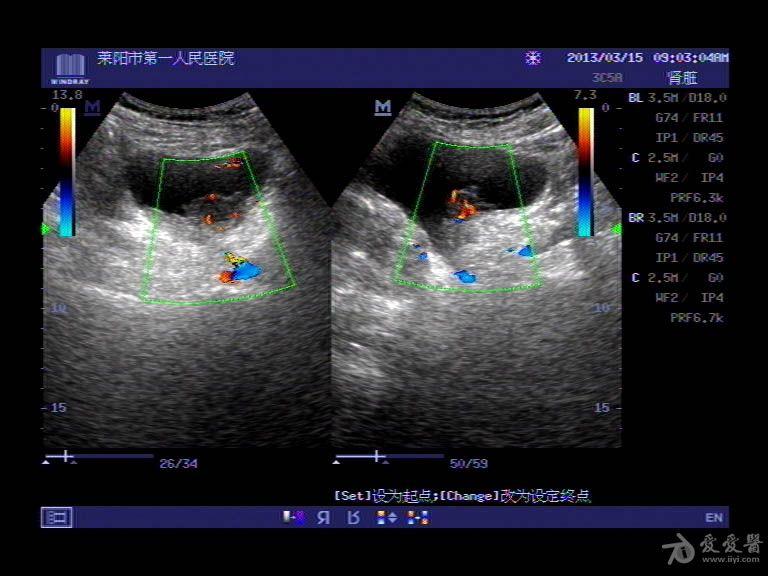

超声入门贴41-----膀胱癌

图片尺寸768x576